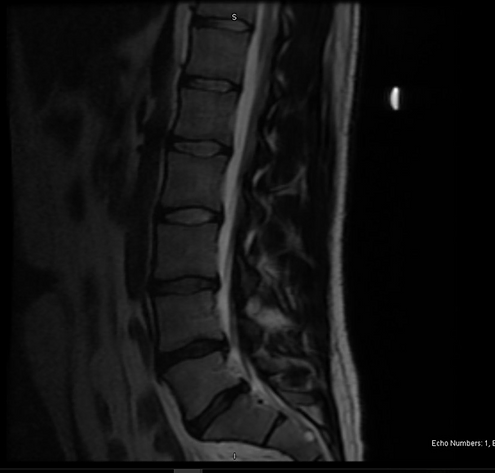

- Obtain a new MRI of the lumbar spine